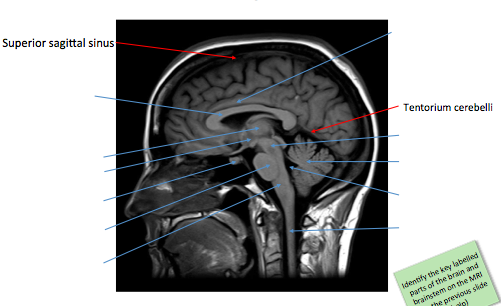

Label the image